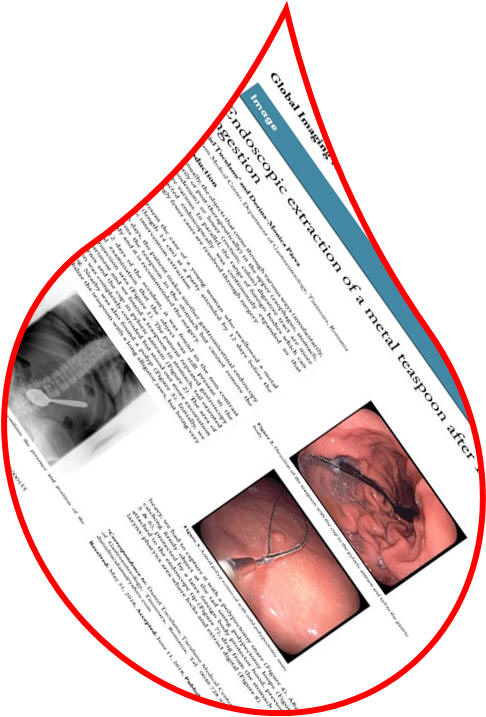

Endoscopia digestivă cu video-capsulă Endoscopic extraction of metal teaspoon Limfomul hepatic primar Nodular bulb-duodenal mucosa